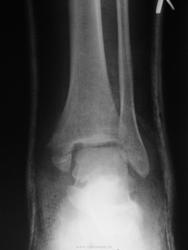

Молодой парень пришёл на приём для контроля после наложения гипса. Снимка сразу после травмы делал не у нас и с собой он их не принёс. Такую травму вижу впервые. Написал о переломе внутренней лодыжке. Таранная кость кажется повреждена и есть латеральный подвывих её. Что есть ещё или что написал лишнего?

Мне кажется, что укладка в боковой проекции выполнена абы как. Медиальная лодыжка поломана. Латеральный подвывих я бы не писала.

Перелом внутренней лодыжки и подвывих. "Задняя лодыжка" - ?

Перелом медиальной лодыжки и заднего края большеберцовой кости. Подвывих бы не писал. И лучше выставлять снимки без гипса.

состояние отломков неудовлетворительное, перелом внутренней лодыжки и заднего края очевиден, как и наружний подвывих. логично искать либо разрыв ДМС либо перелом наружной лодыжки